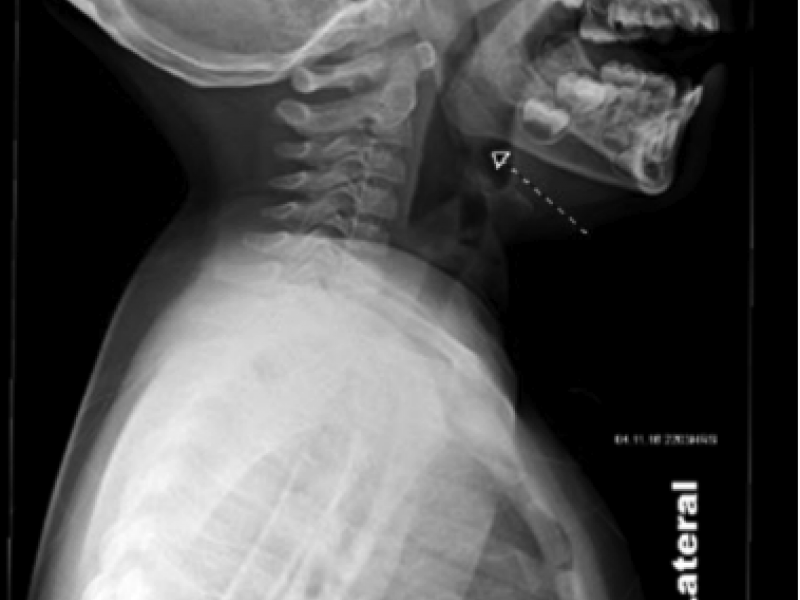

Diagnosis: Fishbone lodged in oropharynx. Presentation